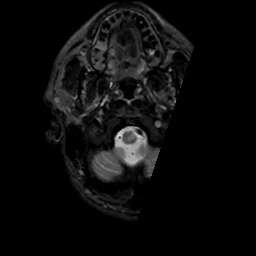

MR Study #4, March 3, 1991 -- Slice #3

[Home][Help][Clinical][Tour 1][Tour 2] Slice 3